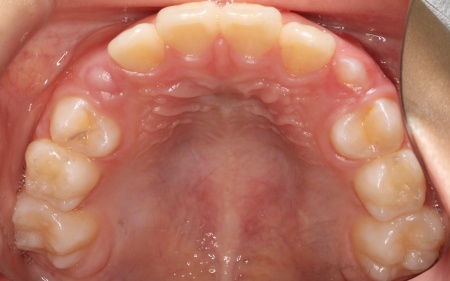

10歳女の子 顎の幅を広げる装置とマウスピース型の矯正装置で反対咬合を改善した症例

拝見したところ、上前歯が下前歯の内側に入り込む「反対咬合(こうごう)」が認められました。

詳しい検査の結果、患者様の反対咬合は歯の位置の問題ではなく、上顎の発育が十分ではないことが主な原因と考えられます。

まずは、「バイオブロック」による治療で上顎の発育を促すこと、その後、前歯の位置を細かく整えるためマウスピース型矯正装置「インビザラインファースト」と、上顎を前方へ引き出す「前方牽引装置」を併用する治療計画を提案しました。

成長期のお子様に使用する矯正装置です。上顎の骨を横方向に拡大して歯が並ぶためのスペースを確保し、反対咬合の改善を図ります。